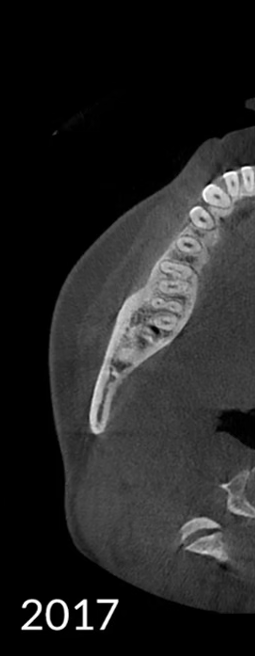

¡Evolución continua, más clara, más precisa!

La tecnología de imágenes de HDXWILL se actualiza constantemente a través de la investigación continua.

Los algoritmos matemáticos que reflejan las propiedades físicas y el avanzado motor de IA aprendido a partir de varios datos trabajan juntos para reducir el ruido y hacer que las estructuras dentales sean más claras.